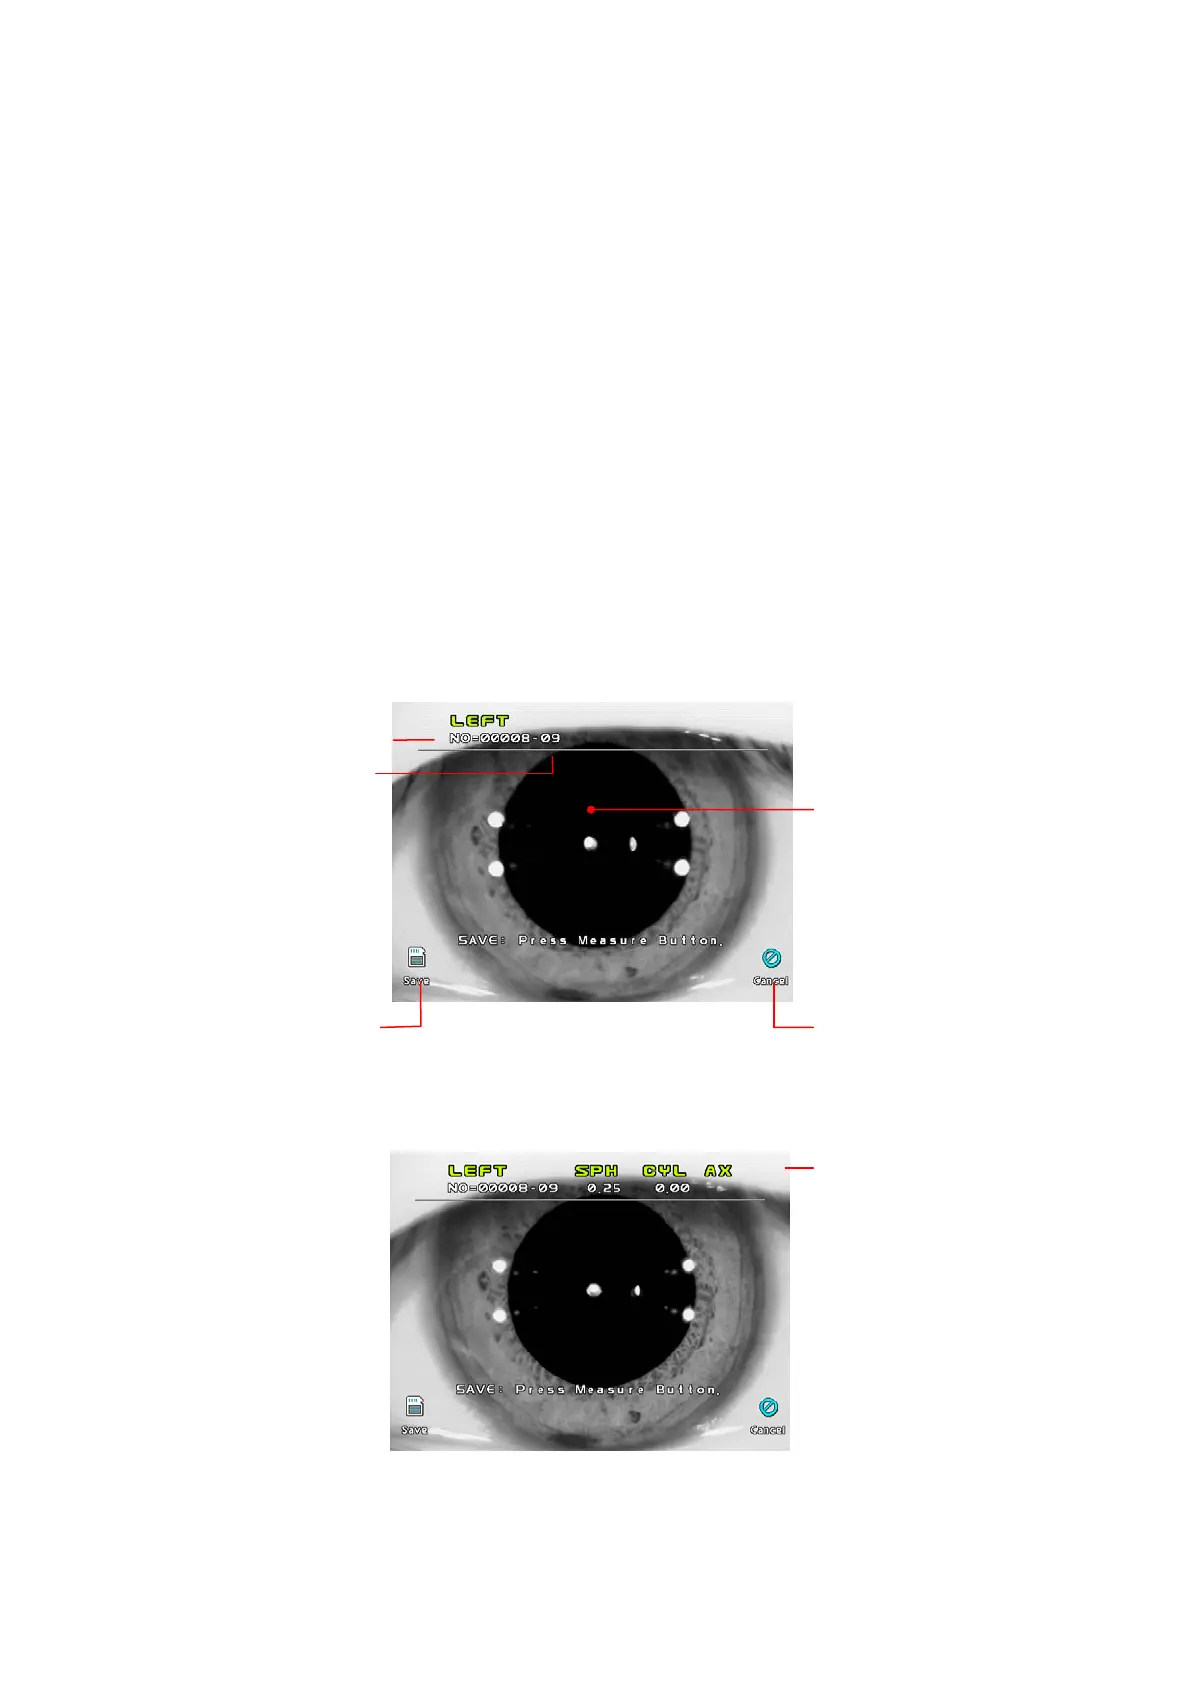

[Freeze Mode Display]

[Freeze/Ref Mode Display]

z Maximum of ten images can be stored for each eye. Each image will have a sub

number (01~10)

Sub Numbe

r

Serial Numbe

Press SAVE button to store

the image into memory.

Press CANCEL button no

t

to store the image.

Result of refractometry

Pupil